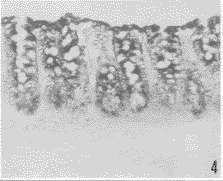

胃小凹的上皮细胞(图1)、大鼠胃底腺的壁细胞(图2)可检测到GnRH受体mRNA杂交反应信号,信号物质分布于胞质,核呈阴性。3段小肠绒毛上皮细胞均检到较强GnRH受体mRNA杂交信号,小肠腺细胞也有GnRH受体mRNA杂交信号,信号物质分布在胞质,胞核为阴性反应(图3)。盲肠、结肠和直肠的粘膜上皮及大肠腺上皮细胞也都检到较强GnRH受体mRNA杂交信号,信号物质也分布在胞质内,胞核为阴性反应(图4)。

图4 结肠粘膜上皮和腺上皮细胞有GnRH受体mRNA阳性杂交信号,信号物质分布在胞质内,胞核阴性。×200

Fig.4 GnRHR mRNA hybridization signals were detected in mucosa epithelial cells and glandular epithelial cells in colon, the signals were distributed in cytoplasm with negative nuclei.×200